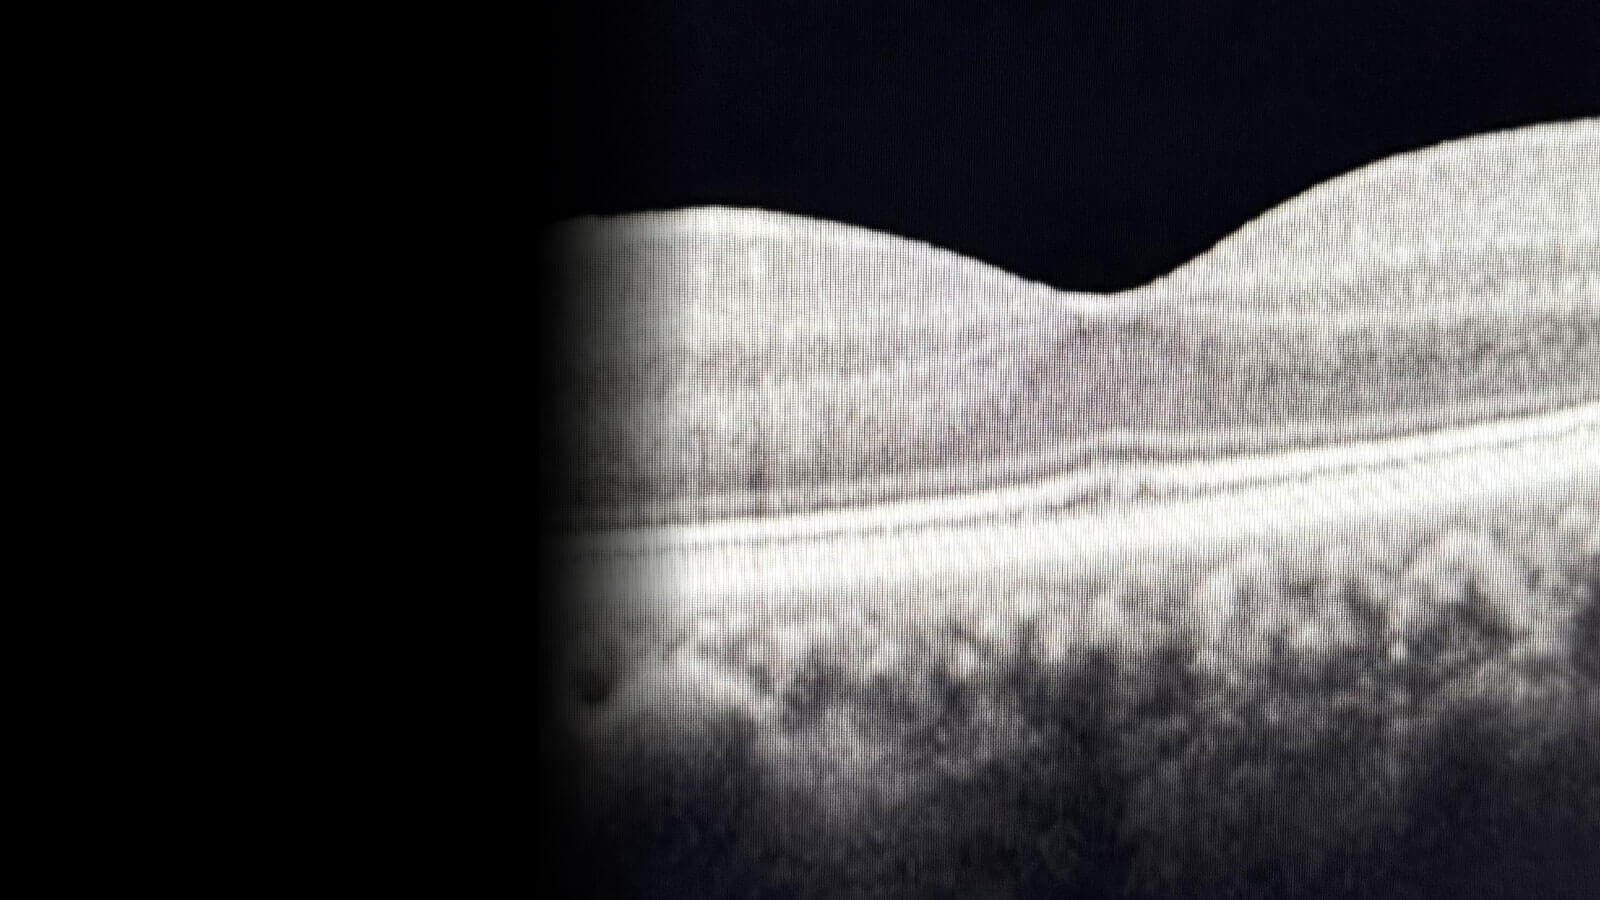

Retina Diseases Image Analysis Reading Center (REDIARC) was founded in 1999.The REDIARC has participated in numerous clinical studies requiring standardized qualitative and quantitative assessments for diabetic retinopathy, diabetic macular edema, macular degeneration, uveitis (active, inactive, non-infectious, Behçet’s disease) as well other retinal pathologies and non-ophthalmic studies requiring retinal safety review utilizing a variety of retinal imaging modalities such as fundus photographs, fluorescein angiograms, autofluorescence and optical coherence tomography (OCT).